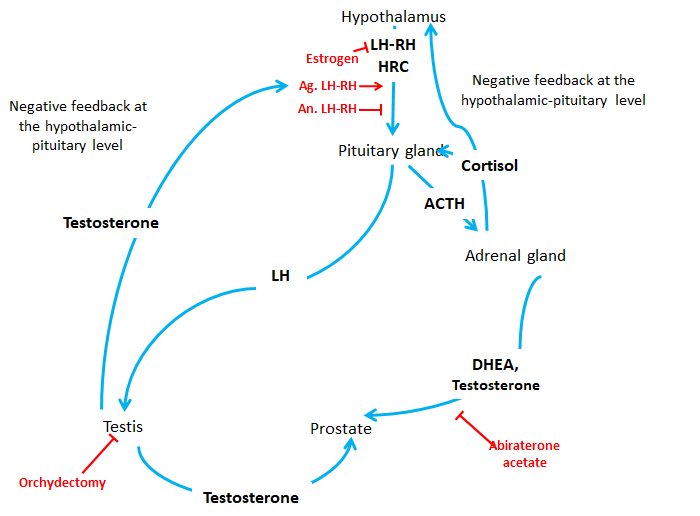

Review Article